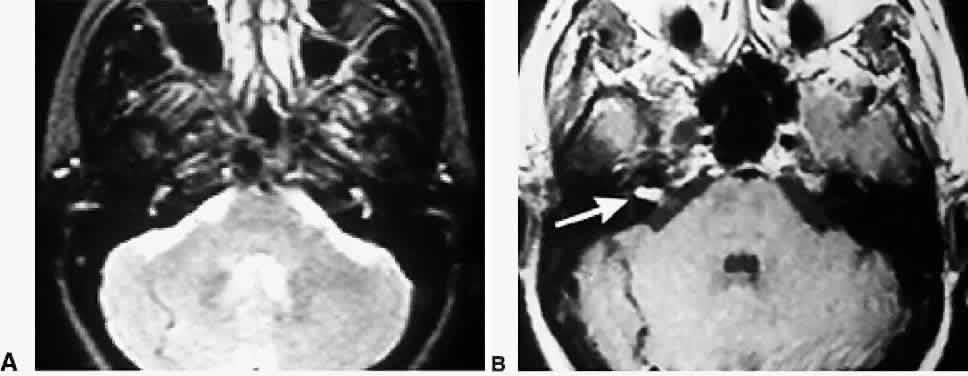

Each SCC innervates two eye muscles by means of a three-neuron arc. The central connections of the horizontal and anterior SCCs on one side are shown in Figure 4. The projections of these two SCCs are shown together because usually they are both involved in vestibular neuritis, the most common cause of severe vertigo. The pathophysiology of vestibular neuritis is diagrammed in Figure 5. This disorder disrupts the superior division of the vestibular nerve.2 Because the Scarpa's ganglion on each side normally is firing at 100 spikes/sec, any loss of activity on one side results in relative excessive excitation from the intact side. This large bias in neural activity causes nystagmus. The direction of nystagmus is determined according to the quick phase, but the vestibular deficit is actually driving the slow phase of the nystagmus. Vestibular neuritis results in a mixed horizontal and torsional nystagmus. This pattern of nystagmus is caused by the innervation pattern of the superior division of the VIIIth nerve on the intact side (recall that the superior division innervates the horizontal and anterior semicircular canals; see Fig. 2). Relative excitation of the horizontal SCC causes horizontal nystagmus with the slow phase toward the side of the lesion. Figure 5 depicts a left-sided lesion, which would cause a right-beating nystagmus. Relative excitation of the anterior SCC causes torsional nystagmus (counterclockwise nystagmus for a left-sided lesion). Because of the confusion over whether to label torsional nystagmus from the perspective of the observer or the patient, the current trend is to assess torsional nystagmus according to the direction of the quick phases toward which the superior poles of both eyes are beating. Thus, a left-sided lesion results in right beating and right torsional nystagmus (see Fig. 5B). There are two other key features of vestibular nystagmus. The intensity of nystagmus is increased when fixation is blocked (Fig. 5B depicts increased nystagmus when the subject looks through Frenzel or 20-diopter lenses), and the intensity of nystagmus also increases when the patient looks in the direction of the quick phases.